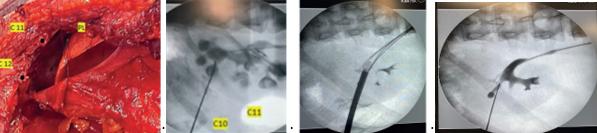

Nefrolitotomia percutanată (NLP) în litiaza coraliformă

Calculii coraliformi sunt calculi ramificați, mari, care umplu pelvisul renal și calicile renale complet sau parțial, în funcție de nivelul de ocupare a sistemului colector. Fig.1 (1) Deși calculii renali sunt mai frecvent întâlniți la bărbați, calculii coraliformi sunt mai des raportați la femei și sunt de obicei unilaterali. (2) Calculii coraliformi sunt calculi de infecție în 49-68% dintre cazuri și prin urmare, termenul de calculi coraliformi se referă în mod tradițional la calculii de struvit.(3) Calculii de struvit, au fost descriși pentru prima dată de un geolog suedez numit Ulex în 1845, sunt compuși din magneziu, amoniu și fosfat și sunt strâns legați de infecția tractului urinar cauzată de organismele producătoare de urează și anume bacteriile Proteus, Klebsiella, Pseudomonas și Staphylococcus (4). Bacteriile metabolizează, de asemenea, citratul din urină și opresc legarea sa protectoare de calciu și fosfat.

1.Chirurgia deschisă

Tratamentul prin chirurgie deschisă presupune pielolitotomia,pielolitotomia combinată cu nefrotomii reglate, marea nefrotomie bivalvă anatrofică și multiple nefrotomii radiare.(Fig.2) (7)

Am combinat pielolitotomia cu nefroscopia flexibilă, în cazuri selective, pentru a extrage calculi caliciali izolați. Toate aceste intervenții deschise au fost practic înlocuite de intervențiile minim invazive și acest lucru a fost posibil datorită progresului tehnologic din ultimii 30 de ani. Apariția laparoscopiei și apoi a intervențiilor asistate robotic au facut posibilă abordarea rinichiului ectopic sau a rinichiului cu pelvis extrarenal poziționat, anterior sau lateral. (8)

2.Nefrolitotomia percutanată standard.

Pacienții preferă o incizie de 1 cm lungime, în comparație cu intervențiile deschise unde rezultatul este o cicatrice greu de acceptat, în special de către femei. (Fig.2)

Intervenția poate fi indicată la pacienții cu un singur rinichi, dar și la pacienții cu litiază renală și insuficiență renală, acestia au însă nevoie de asistență metabolică si un echilibru strict de intrare / ieșire a lichidului de irigare. Poate rezolva și situații speciale, cum ar fi rinichiul în potcoavă, pacienți cu obezitate morbidă, dizabilități locomotorii, rinichi hipermobil, afecțiuni asociate ureterale, pacienți purtători de sonde JJ, a celor cu nefrostomii sau ureterostomii. (Fig.3)

În plus, pacienții sunt mai dispuși să accepte o nefrostomie pentru câteva zile, decât stentul JJ necesar după o ESWL, sau o ureteroscopie flexibilă. Procedura este reproductibilă; prezentăm mai jos un pacient cu cicatrice de pielolitotomie dreaptă și 2 proceduri NLP anterioare. (Fig 3 C)

NLP, principii generale

Rezultatele acestei intervenții miraculoase, dar nu lipsită de riscuri, depind de măsura în care sunt respectate principiile tehnicii și mai ales de modul în care acestea sunt aplicate. Experiența însă, îți poate spune când și cum să faci acest lucru.

Securitatea pacientului trebuie să fie prioritatea majoră pentru practician, iar acest deziderat l-am îmbrățișat pe tot parcursul celor 25 de ani de când fac această intervenție.

Nefrolitotomia percutanată ar trebui să se efectuează numai pe un rinichi funcțional. Strategia depinde de compoziția calculului, dimensiuni, densitate, starea rinichilor, comorbiditățile pacientului, dotarea serviciului și mai ales, de competența câștigată și dovedită într-un centru de excelență de către practician. Orice istoric chirurgical anterior este important.Trebuie apoi ținut cont de contraindicațiile absolute și relative pentru: sarcină, tulburări de sângerare (probleme de coagulare netratate), afecțiuni pulmonare severe, diformități ale coloanei, in-

Fig.1

Fig.2

În situații deosebite, am combinat nefroscopul rigid cu nefroscopia flexibilă. (Fig.4B) Această combinație crează însă o problemă legată de schimbarea camerelor și a surselor de lumină, consumatoare de timp. Pentru a evita acest lucru s-au imaginat nefroscoape multifuncționale, cu teci multifunctionale. (9)

3.Miniperc singur sau combinat cu NLP

În cazuri selective, asociez Miniperc nefrolitotomiei percutanate standard, considerând că o puncție minimă suplimentară, controlată, este mai sigură decât încercarea forțată, necontrolată, de a extrage un calcul dintr-o zonă care nu este accesibilă nefroscopului rigid, NLP pas cu pas

Pregătirea preoperatorie a pacientului trebuie sa fie extrem de minuțioasă în ceea ce privește diagnosticul complet și strategia operatoare. Sunt pași de urmat care cuprind: antibioterapia properatorie (prefer o săptămână la cei infectați), analize obișnuite și specifice în funcție de comorbidități, poziție operatorie, alegerea accesului în rinichi (prefer monoplanar, fluoroscopic), alegerea anesteziei (prefer rahidiană).

Este extrem de importantă analiza preoperatorie a explorărilor (prefer CT și UPG pentru a determina configurația finală a sistemului pielocalicial) care stabilesc dimensiunea, volumul calculului (cu consecințe privind estimarea timpului necesar), identificarea calicelor posterioare (rinichi tip Brodel, Hodson) (Fig 5B), decizia calicelui de puncționat (inferior sau superior), decizia puncțiilor mul-

tiple (superior, mijlociu, inferior), puncția și dilatația via fornix, pentru obținerea unei rate cât mai mari de ’’stone free’’ și toate măsurile necesare pentru evitarea complicațiilor majore. Decizia finală a abordului calicial a fost întotdeauna luată după ureteropielografia retrogradă (Fig.5) și după întoarcerea pacientului în poziția procubit (harta intervenției, Fig.5 C (10)), poziție pe care am folosit-o întodeauna. Uneori, strategia de puncționare adoptată pe baza informațiile imagistice se poate modifica după așezarea pacientului în procubit ventral (rinichiul ascensionează). Sunt încă dispute în literatură legate de poziția pacientului în timpul intervenției. Mă aliniez celor care consideră că, fiecare practician trebuie să folosească tehnica în care a fost instruit, în interesul securității pacientului. (11)

De altfel, este știut că numărul pacienților care au nevoie cu adevărat de poziția în decubit dorsal (supine), este la fel de mic ca și numărul pacienților pentru care poziția procubit ventral este contraindicată. La fiecare pacient se poate elabora un scor de dificultate, în funcție de duritatea calculului (unități Haunsfild), de volumul calculului (între 5000-20000 și peste 20000 mm cubi) și de favorabilitatea calicelui ce urmează a fi puncționat.

De cele mai multe ori, în litiaza coraliformă calculii blochează calicele, făcând dificil accesul în infundibul spre bazinet, fiind nevoie de o negociere a ghidurilor cu calculii din calice.

Dilatarea traiectului am efectuat-o întotdeauna cu dilatatoarele metalice Alken la nivelul calicelui, pentru evitarea lezării infundibulului și a bazinetului. Dilatarea se face sub control fluoroscopic, cunoscând riscul de pierdere a traiectului. Li-

totriția cea mai des folosită este cu energie ultrasonică, ce permite și aspirația, un element foarte important în economia intervenției. Drenajul cavităților l-am făcut cu una sau mai multe nefrostomii, iar drenajul hemostatic, când a fost cazul, cu cateter Foley. Urină prelevată din pielonul afectat și fragmente litiazice extrase sunt trimise pentru culturi și antibiogramă la sfârșitul intervenției. La externare, le recomandăm pacienților analiza calculilor, pentru a completa tratamentul și a preveni recidivele. Pentru securitatea pacientului am mers pe (când a fost necesar) decizia de a efectua intervenția în doi timpi. (Fig.6)

Abordarea calicelui inferior

Este calicele cel mai des folosit în abordul percutanat al litiazei deși, este cel mai neprietenos și respectă cel mai puțin configurația anterioară și posterioară, conform studiilor binecunoscute ale lui Sampaio. (12)

Am folosit puncția calicelui inferior (cea mai puțin lipsită de riscuri) în litiaza coraliformă atunci când unghiul dintre calicele inferior și superior este permisiv și când distanța de la piele la calcul este acceptabilă (dimensiunea psoasului). Unghiul permisiv (Fig.7 A) oferă un traiect drept de-a lungul axei rinichiului și permite accesul la polul superior fără o presiune excesivă a instrumentelor rigide.

Abordul calicelui superior

Abordul calculului coraliform prin calicele superior, deși este greu de manageriat, este cel mai recomandat, datorită direcției de acțiune în lungul axului rinichiului. Altfel spus, pentru că permite litotriția în calicele superior, bazinet dar și in calicele inferior.Tangențial și mai ales când rinichiul este hidronefrotic, poate ajunge și în calicele mijlociu. Personal, puncționez calicele superior din lateral (dispoziția calicelor nu este anterior și posterior), întercostal (Fig.8B) și rar de sus (Fig.8C). Dacă puncția se face în infundibul, există riscul interceptării arterei segmentare posterioare (Fig 8D), care merge pe fața posterioară a infundibulului în 57 % dintre cazuri. (Sampaio et all)

1. Accesul prin calicele lateral superior (Fig.8B)

Fig.3

Fig.4

Fig.5

Relații strânse între coastele 11 (C11) și 12 (C12), plămânul (PL) și diafragmă (D). Imaginea fluoroscopică arată traiectoria puncției în calicele superior și relațiile acesteia cu coastele a 11-a și a 12-a.

2. Accesul calicelui superior de sus (Fig 8C)

Presupune un risc major de interceptare a unor structuri adiacente. Se va face atunci când experiența acumulată, imagistica și condițiile pacientului îți vor permite acest abord.

Abordarea caliciului superior necesită câteva manevre care permit coborârea rinichiului, facilitând puncția și evitând interceptarea pleurei, ficatului, splinei, plămânului.

1. Mobilizarea renală, 4-5 cm prin inspirație profundă (rinichi neoperat) urmată de puncția calicelui. (Fig.9)

2. Mobilizarea rinichiului se poate face printr-o puncție suplimentară cu un ac de puncție (Fig.9), asupra căruia se va crea o presiune de mobilizare în jos a rinichiului.

3. Puncție suplimentară urmată de dilatație Alken 12.14 F asigurând o tracționare în jos a rinichiului. (Fig.9C) Se vor face apoi puncția și dilatația care permit litotriția.Tractul supracostal 10 este foarte riscant, motiv pentru care nu este recomandat. Pentru toate tracturile supracostale este important să ne asigurăm că teaca de acces rămâne în rinichi în timpul procedurii, pentru evitarea inundării cavității pleurale.

Puncția calicială multiplă

Mai multe tracturi sunt decise și individualizate pentru fiecare pacient în momentul intervenției chirurgicale. Pentru controlul și securitatea intervenției, puncțiile trebuie efectuate la începutul intervenției și asigurate cu ghiduri de așteptare. Sunt multe studii în literatură, pro și contra, legate de riscul de sângerări intra și postoperatorii. (Fig.5)

Ghidurile AUA sugerează că mai multe tracturi sunt eficiente și sigure în litiaza coraliformă, cu o rată de ’’stone free’’ de 79% și o rată de complicații imediate de 15%. (13)

Calculul ocupă calicele

Accesul renal și dilatarea în calice, în calculul coraliform, sunt dificile și există un risc major de pierdere a traiectului operator. Sunt câteva manevre binecunoscute și recomandate, pe care le folosesc când ghidul nu trece de calcul și se încolăcește în calice.

1. Schimbarea direcției acului, retrageri și avansări minime sub control fluoroscopic, fără a pierde contactul cu calculul.

Fig.6

Fig.10

Fig.7

Fig.8

Fig.9